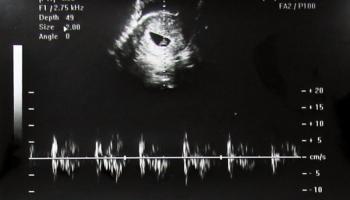

8. 임신 12주 차 - 2.88cm